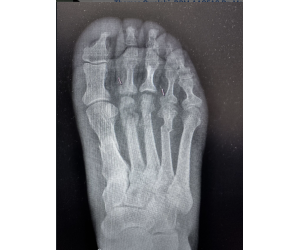

Correcting MIS Lapidus

Dr. Kris Di Nucci

MIS surgeons — here is a patient who presents 10 months after an MIS Lapidus arthrodesis. She reports recurrence of her bunion and mild sesamoid...